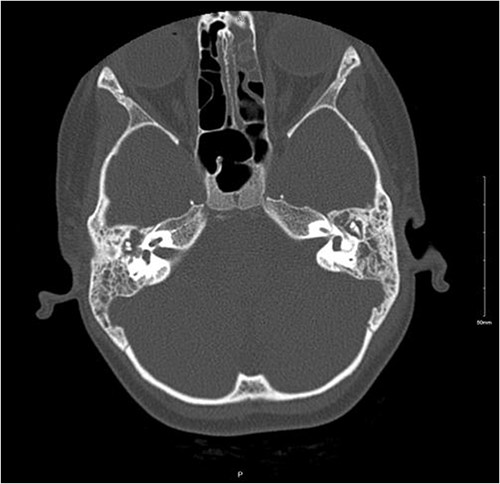

An 8-year-old female patient presented with recurrent episodes of acute otitis media (AOM) and foul-smelling yellowish discharge from the left ear with hearing loss, after receiving multiple courses of antibiotics with only slight improvement. Otoscopic examination showed left small central perforation with minimal granulation tissue and right middle ear effusion. The patient was afebrile with no constitutional symptoms. A CT scan of the temporal bone revealed signs of bilateral mastoid and middle ear opacification with left mastoid cortical erosion, an overlying soft tissue swelling, and a parapharyngeal hypodense collection that likely represents an abscess (Fig. 1). Therefore, the patient was hospitalized for further investigations.

Non-enhanced axial CT scan of temporal bone showing bony remodeling suggestive of chronic otomastoiditis.